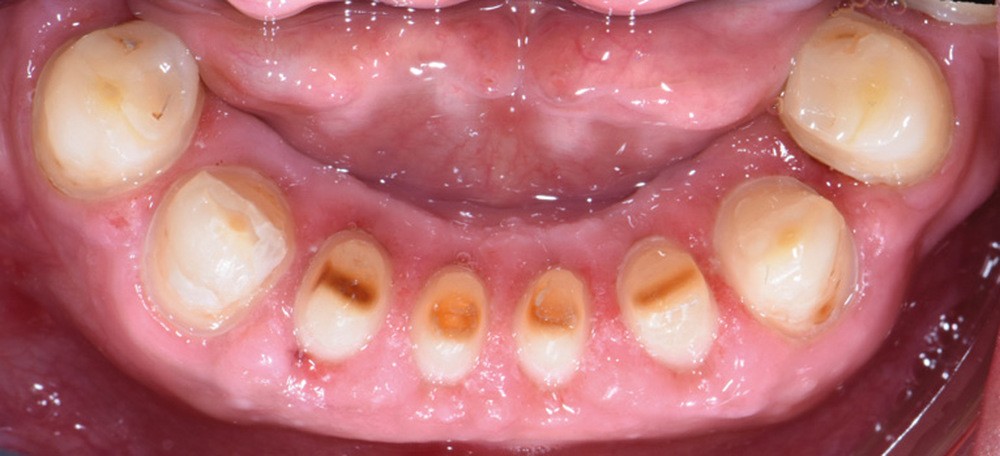

Au vu du contexte para-fonctionnel et de l’étendue de la perte tissulaire, des coiffes périphériques minimalement invasives ont été choisies afin de restaurer l’esthétique et la fonction. Actuellement, aucun consensus n’est fait sur le choix du matériau d’infrastructure à privilégier. Les matériaux hybrides usinables présentent des propriétés mécaniques, physiques et biologiques intéressantes en contexte d’usure sévère (e.g., module d’élasticité, résistance à la propagation de fêlures, facilité de réintervention). Une réhabilitation globale avec remontée de dimension verticale d’occlusion (DVO) par l’intermédiaire de coiffes composites renforcés en nano-céramiques est décrite.